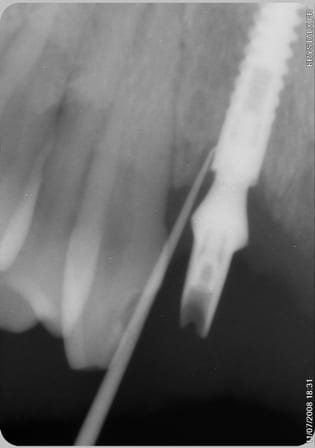

voila la rx du bridge en place, plus de fistule et apparement pas d'augmentation de la perte osseuse .

Perimplantite 2 fk11pb - Eugenol